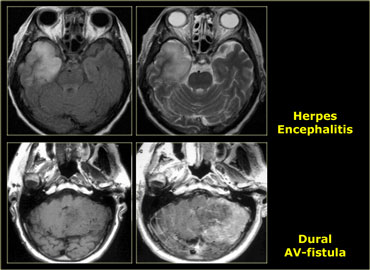

Tumor Mimics

Many non-tumorous lesions can mimic a brain tumor.

Abscesses can mimic metastases.

Multiple sclerosis can present with a mass-like lesion with enhancement, also known as tumefactive multiple sclerosis..

In the parasellar region one should always consider the possibility of a aneurysm.

Infections and vascular lesions can also mimic a CNS tumor.